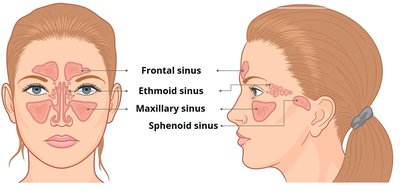

Nasal Cavity and Paranasal Sinuses

The nasal cavity provides an airway, moistens and warms air, filters particles, resonates sound for speech, and houses olfactory receptors. The paranasal sinuses open into the nasal cavity and are lined by respiratory mucosa, performing similar functions.